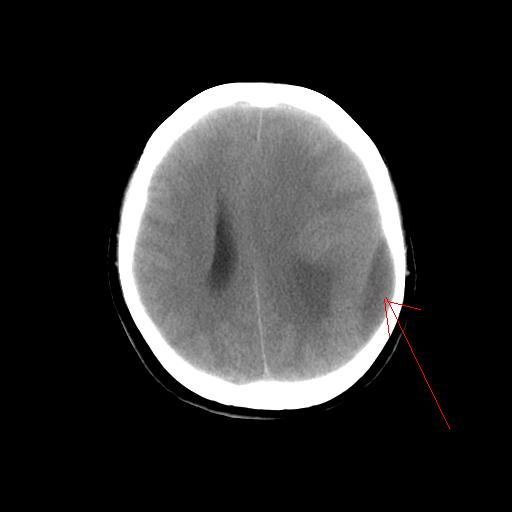

标题: CT14513:女性41岁,头部不适二月余,其它病史不详。请分析 [打印本页]

1.考虑:左侧颞顶叶星形细胞瘤。2.大脑镰下疝。

支持!但楼主所提示处颅骨明显受压变薄,是否有合并蛛网膜囊肿或局部硬膜下水瘤的可能?脑穿通畸形暂不予以考虑:明显占位表现;病侧脑室无扩张;病灶不是较明确的脑脊液密度;边界不清晰。还是mri检查吧,提供的有价值信息更多一些,至少可以排除或肯定蛛网膜囊肿或局部硬膜下水瘤的存在。

1)考虑左侧颞顶叶胶质瘤。2)左侧颞顶部慢性硬膜下血肿?3)大脑镰下疝。